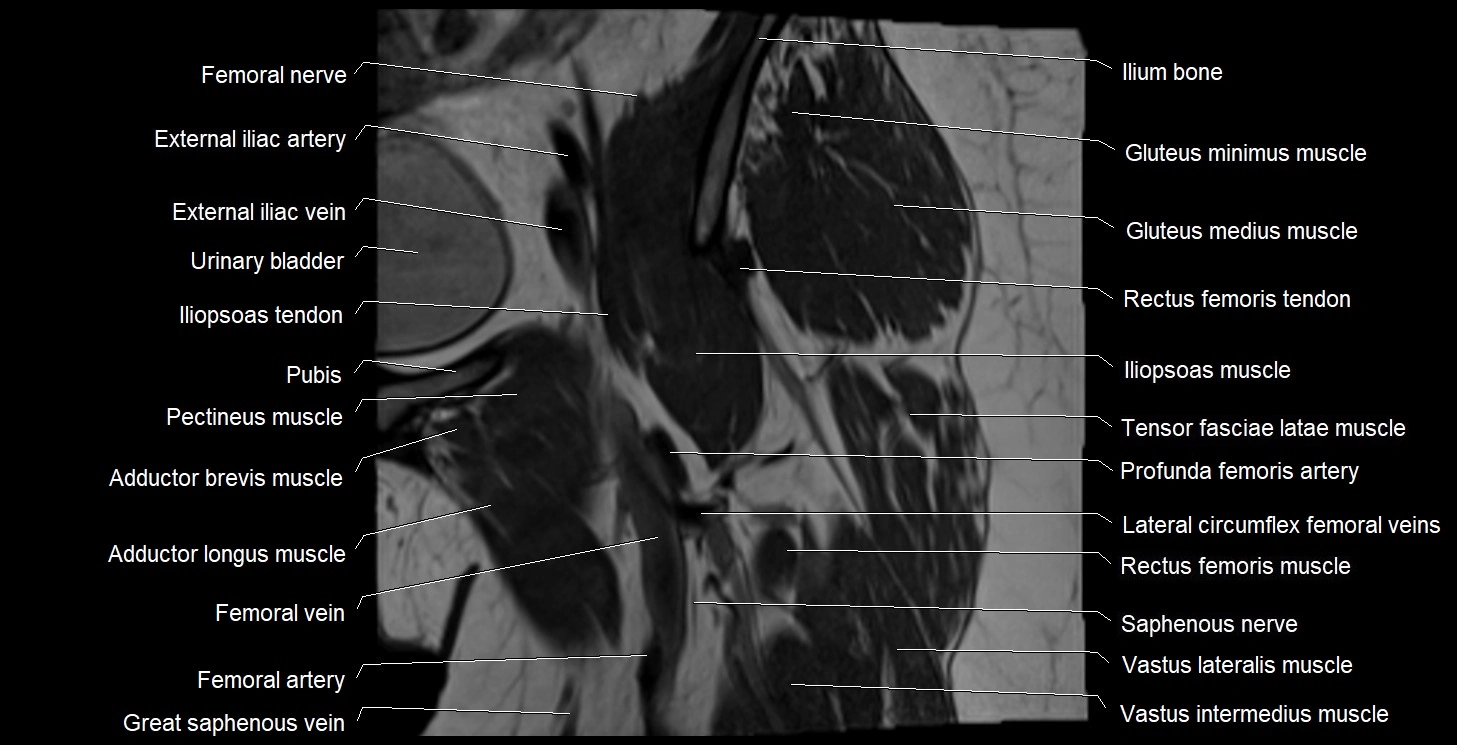

- External iliac artery

- External iliac vein

- Femoral nerve

- Femoral vein

- Femoral artery

- Femur

- Iliopsoas muscle

- Iliopsoas tendon

- Lateral circumflex femoral veins

- Lateral femoral cutaneous nerve

- Saphenous nerve

- Tensor fasciae latae muscle

- Vastus intermedius muscle

- Vastus lateralis muscle